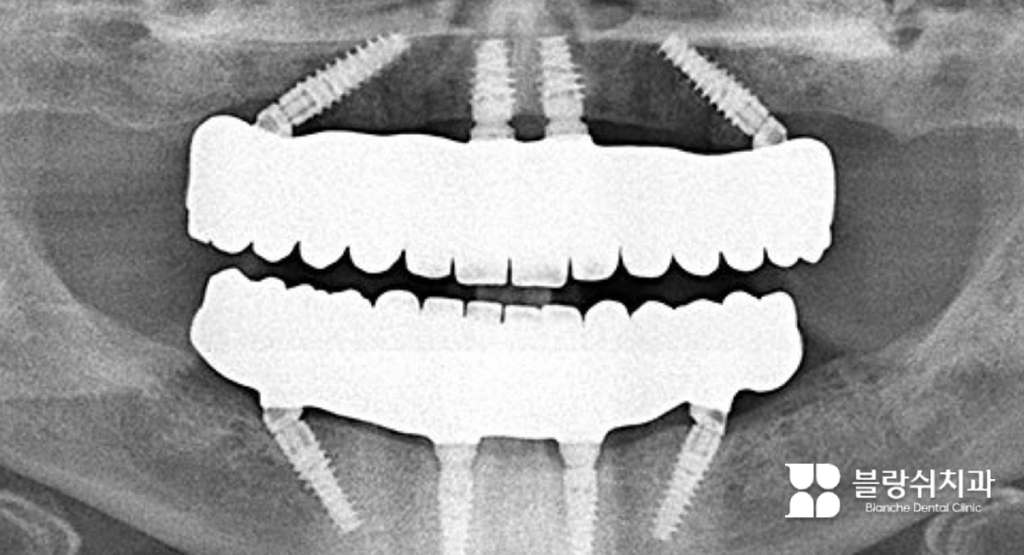

디지털 풀아치 임플란트는 치아가 거의 없거나 하나도 없는 상태(무치악)에서 임플란트 몇 개로 전체 치아를 한 번에 회복하는 치료 방식입니다. 보통 임플란트 8~12개를 식립해 28개의 치아 기능을 하나의 보철물(풀아치)로 구현합니다.

기존 전체 임플란트는 치아 하나당 임플란트를 심는 방식이지만, 디지털 풀아치는 다릅니다. 뼈가 단단한 위치를 선별해 식립하고 하중을 분산시키는 구조가 핵심입니다. 여기에 3D CT, 구강 스캔, 컴퓨터 시뮬레이션을 활용한 디지털 수술 계획이 결합됩니다.

• (3) 적은 개수로도 전체 치아 역할을 합니다 사람의 치아는 총 28개지만, 28개의 임플란트를 모두 심을 필요는 없습니다. 디지털 풀아치는 힘을 잘 분산시키는 설계로 8~12개 정도만으로도 전체 치아 기능을 할 수 있습니다. 이는 오랜 연구와 기술 발전으로 가능해진 방식으로, 지금은 전 세계에서 검증된 치료 방법입니다.